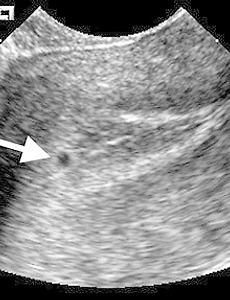

intradecidual sign Sonographic Appearances of Normal Intrauterine G-sac: It should be possible to visualize a normal G-sac via TVS between 4.5 to 5 weeks of MGA. The threshold level identifies the earliest we can visualize the sac :- 4 weeks + 3 days. The discriminatory level indicates when we should always see the sac :- 5 weeks + 2 days. The earliest appearance of gestation on TVS is referred to as Intra Decidua.. 2013. 12. 15. 이전 1 2 다음